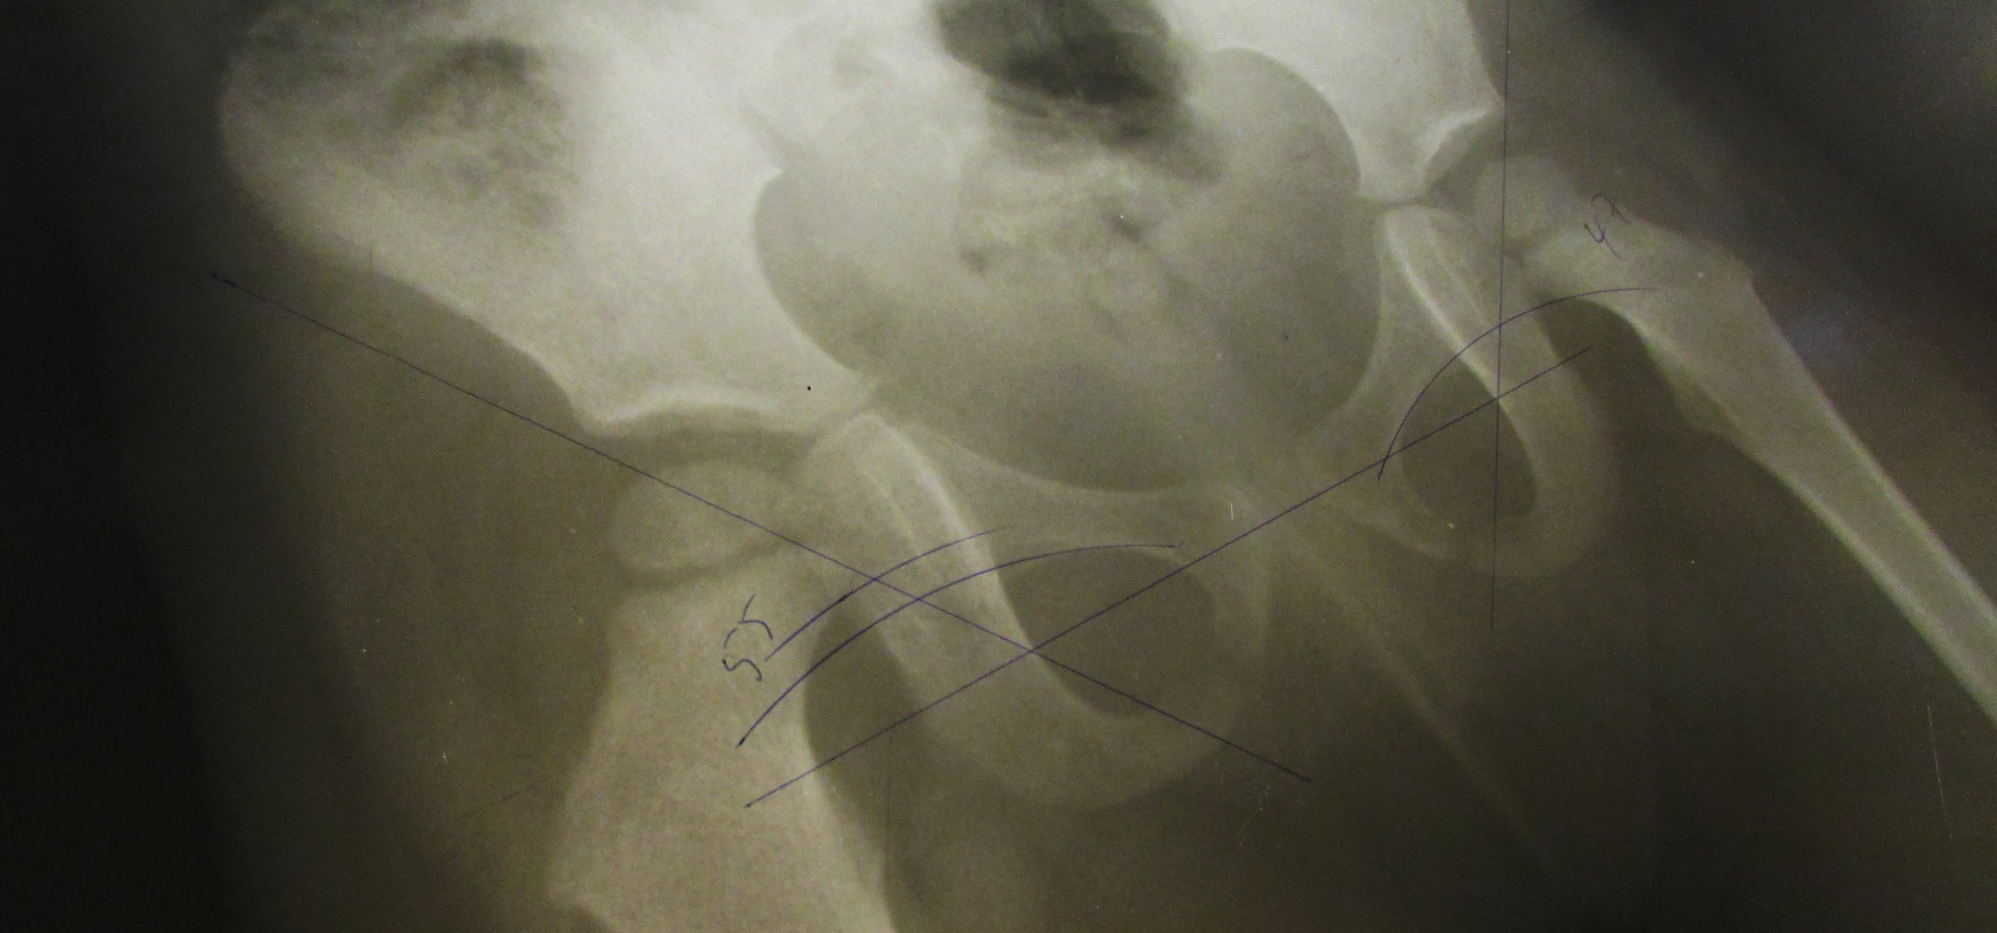

X-ray of a patient with hip dysplasia.